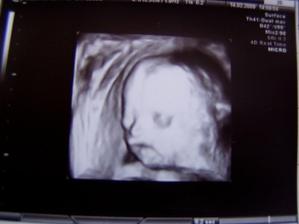

14.02.09 sme dostali krasny Valentinsky darcek.Boli sme na morfologickom ultrazvuku a pan doktor nas pekne pomeral a povazil.Mame uz 464 gramov a krasne rastieme.A mame pipika takze cakame Filipka